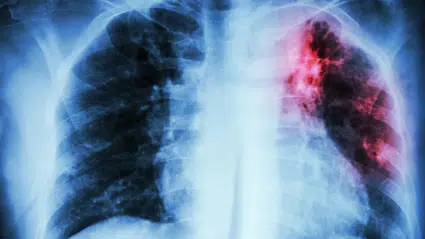

Muhalif. SAĞLIK DSÖ açıkladı: 10 yıl içinde ilk defa arttı

DSÖ açıkladı: 10 yıl içinde ilk defa arttı

Dünya Sağlık Örgütü (DSÖ), koronavirüs ile mücadelenin sağlık sisteminde yarattığı boşluk nedeniyle dünyada tüberküloz kaynaklı ölümlerin son 10 yıl içinde ilk defa artış gösterdiğini açıkladı.

DSÖ'nün yayımladığı 2021 Tüberküloz Raporu'nda, dünya genelinde 2019 ve 2020'deki tüberküloz vakaları incelendi.

Raporda tüberküloz tedavilerine ayırılan kaynağın geçen yıldan bu yana koronavirüse aktarıldığı ve bu nedenle tüberküloz tedavisi için gerekli hizmetlerin birçok ülkede yeterli oranda sağlanamadığı belirtildi.

2019'da dünyada tüberkülozdan 1,2 milyon kişinin hayatını kaybettiği bilgisinin yer aldığı raporda, 2020'de tespit edilebilen tüberküloz ölümlerinin 1,5 milyona çıkarak bu rakamın son 10 yıl içinde ilk defa artış gösterdi vurgulandı.

Raporda ayrıca DSÖ'nün tahminlerine göre 2020'de 4,1 milyon kişinin tüberkülozla mücadele ettiği fakat teşhis konulamadığı öne sürülerek, bu rakamın da 2019'da 2,9 milyon olduğu kaydedildi.

ÖLÜMLER İLERLEYEN YILLARDA ARTABİLİR

Tüberkülozun 30 ülkede etkisini giderek artırdığı belirtilen raporda, 2021 ve 2022'de can kayıplarının daha da artabileceği uyarısı yapıldı.

DSÖ Genel Direktörü Dr. Tedros Adhanom Ghebreyesus, örgütün Cenevre'deki merkezinde rapora ilişkin düzenlediği sanal basın toplantısında, "Söz konusu rapor, küresel pandemiden ötürü tüberkülozla mücadelede kat edilmiş bunca yıllık ilerlemelerin heba olabileceği yönündeki endişelerimizi doğruluyor" dedi.

Dr. Ghebreyesus, tüberküloz ölümlerindeki artışın tüm dünyaya bir uyarı niteliği taşıdığını belirtti ve "Bu eski, ancak önlenebilir hastalıktan etkilenen milyonlarca insan için teşhis, tedavi ve bakımdaki boşlukları kapatmak üzere yatırımlara acil ihtiyaç var" şeklinde konuştu.

Solunum yoluyla akciğerlere yerleşen ve verem olarak da bilinen tüberküloz, dünya nüfusunun yaklaşık dörtte biri tarafından gizli olarak taşınıyor.

Akciğerlerin yanı sıra boşaltım ve sindirim sistemleriyle omurga, böbrekler ve karın boşluğu gibi farklı bölgeleri etkileyen tüberküloz, tutuluma yol açtığı bölgeye göre karın ağrısı, sindirim ve emilim sorunları, karında sıvı birikimi, karaciğer ve dalak büyümesi, eklemlerde iltihaplanma, lenf bezlerinde büyüme gibi farklı belirtilere de yol açabiliyor.